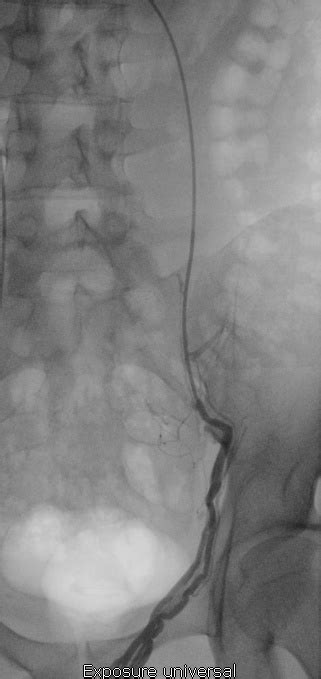

Embolisation varices pelviennes Centre Varices Pelviennes

Varicocele Embolization — Varicocele Doctor Varicocele Doctor Medium. The embolisation was at the Royal Berkshire hospital. Mon varicocèle semblait avoir diminué, plus de douleurs au testicule, bref ça partait bien